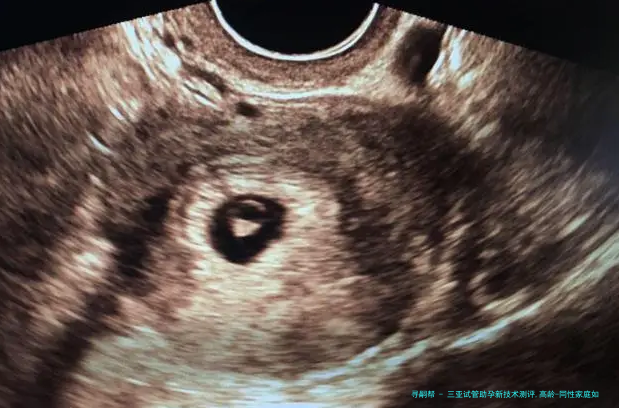

胚胎植入前基因学检查(PGD/PGS)已成为三亚主要潮流机构的标配,新一代测序技术将染色体异样检出率提升至99%以上,大幅减少高龄夫妻因卵子老化导致的早产风险。更前端的试探集结在CRISPR基因编辑,可修复地中海贫血、脊髓性肌肉萎缩症等单基因突变,虽暂处临床研究阶段,但为遗传性疾病家庭提供了新可能。

胚宝宝动作态监测:Time-lapse系统通过每小时捉拿超十万帧影像,结合AI算法分析胚胎分裂速度、细胞对称性等200+参数,较守旧样子学评估将优质胚胎检查筛选准确程度提高30%-40%。

玻璃化冷冻技术使胚胎复苏存活率达百分之九十八,卵子保存复苏率进展百分之九十一。针对卵巢功能衰落者,线粒体体替换技术通过替换衰老细胞器,使42岁以上女性活产率从百分之十五跃升至28.7%。

三十八岁以上女性卵子非整倍体率超60%,需首先选择备有PGT-A(非整倍体筛查) 技术的机构,结合AI预测模型筛查染色体正常胚胎,将四十二岁临床妊娠率从12%提至39%。反复移植失败者,可以借助无创胚胎基因诊断(niPGT) 通过培育液游离DNA筛查,防止活检伤害胚胎,活产率提升至75%。